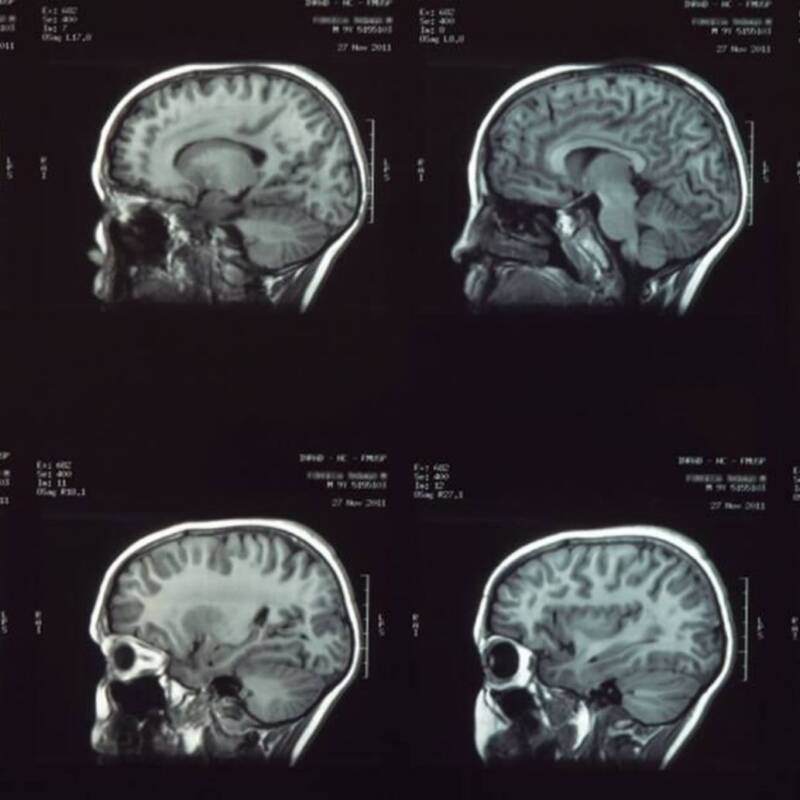

Los especialistas analizaron imĆ”genes cerebrales de mĆ”s de 150 voluntarios de entre 11 y 25 aƱos. Sus hallazgos revelaron modificaciones en la conectividad entre regiones clave, lo que podrĆa relacionarse con una mejora en la capacidad de evaluar riesgos y planificar acciones de manera mĆ”s eficiente.